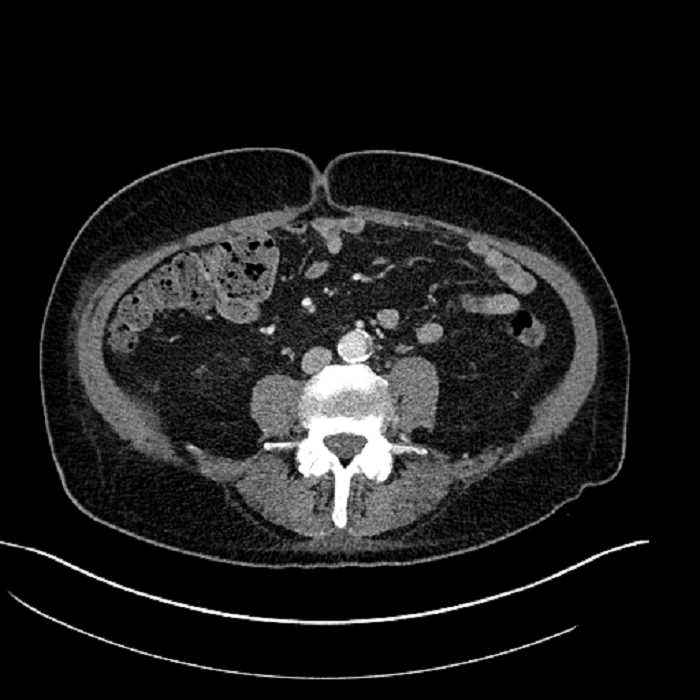

Age: 63

Sex: Male

Indication: Abdominal pain

• Mild mural thickening of a segment of the sigmoid colon with adjacent fat stranding and a 1.5 cm fluid and gas collection along the tip of an inflamed diverticulum

• Loss of the normal fat plane between this collection and adjacent loops of small bowel, which demonstrate mural thickening

• High grade stenosis of the left common iliac artery, with the left internal and external iliac arteries remaining patent

Acute sigmoid diverticulitis complicated by a small contained perforation and a large abscess in the right hepatic lobe. Additional small subcapsular abscesses along the anterior margin of the left hepatic lobe.

Additionally, loss of the normal fat plane between the peridiverticular collection and adjacent thickened loops of small bowel raises the potential for an enterocolonic fistula.

High grade stenosis of the left common iliac artery. The left external and internal iliac arteries are patent.

Hepatic abscess showing the double target sign with low density internally surrounded by a thin inner enhancing rim (red arrow) and ill-defined outer low density rim (yellow arrow). Blue arrow indicates an internal septation. Red arrows: additional smaller subcapsular abscesses. Red arrow: focal contained perforation associated with diverticulitis.